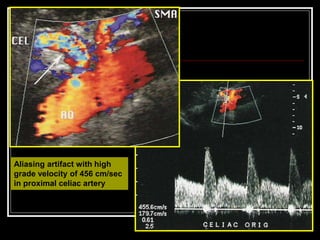

USG & Doppler Findings

 Grey scale evaluation :

- atherosclerotic plaque or thrombus at the site of stenosis /

occlusion.

 Color Doppler :

 Luminal narrowing

 Color flow aliasing

 Reversal of flow

 Collateral vessels

Normal velocities

Range of normal blood flow velocities in

 Celiac artery : 98 – 105 cm/sec

 SMA : 97 – 142 cm/sec

 IMA : 93 -189 cm/sec

 Widely accepted criteria are based on the

PSV measurements of mesenteric arteries

 Pulsed Doppler :

Elevated velocities

 PSV of > 200 cm/sec in celiac artery

 PSV of > 275 cm/sec in SMA are predictive of

stenosis of 70% or more.

 Mesenteric : Aortic ratio greater than 3 is

associated with hemodynamically significant

stenosis .

Aliasing artifact with high

grade velocity of 456 cm/sec

in proximal celiac artery

SMA stenosis with high velocity and

low velocity in post stenotic zone